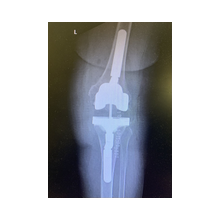

Aşınmış, hasar görmüş ya da eklem yüzeyleri tamamen bozulmuş diz ekleminin, yapay bir eklemle değiştirme işlemidir. Ameliyatta, ağrıya neden olan hasarlı kemik ve kıkırdak dokular çıkarılarak; yerine metal ve özel plastikten yapılmış, uzun ömürlü bir protez yerleştirilir. Bu sayede diz, tekrar ağrısız ve stabil bir şekilde çalışır hale gelir.

Eklem yüzeyleri özel kılavuzlar yardımı ile temizlendikten sonra metal protez eklem yüzeylerine bir kemik çimentosu ile adapte diyoruz. Bu iki metal yüzeyin sürtünmesini azaltmak için polietilenden yapılmış özel bir plastik tabakayı sisteme dahil ediyoruz.